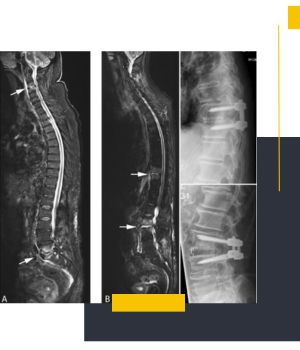

پیگیری درمان‌های ارتوپدی مثل قبل و بعد از جراحی یا بریس

پیگیری درمان‌های اسکلتی: این تکنولوژی ویژه روند درمان بنا به توصیه پزشک را پیش از جراحی، پس از جراحی یا در برنامه‌های فیزیوتراپی دقیق‌تر پیگیری می‌کند.

مقایسه وضعیت قبل و بعد درمان: تحلیل تصاویر تهیه‌ شده در بازه‌های زمانی مختلف، میزان اثربخشی مداخلات درمانی و تغییرات ساختاری را به پزشک نشان می‌دهد.

امکان پیگیری درمان و مقایسه تصاویر در بازه‌های مختلف: ویژگی ترکیب تصاویر در این روش مقایسه پیش از درمان، حین درمان و پس از درمان را ساده می‌سازد. پزشکان می‌توانند روند بهبود یا تغییرات ساختاری را با جزئیات بررسی کنند.